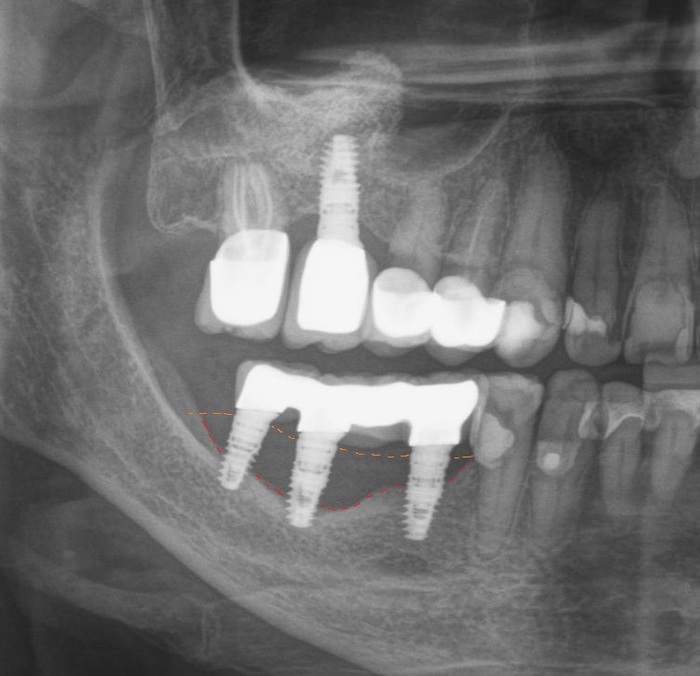

Ниже, на панорамном снимке зубов, мы наблюдаем критичную убыль костной ткани вокруг имплантатов на верхней челюсти.

Оранжевая пунктирная линия - было,

красная - стало.